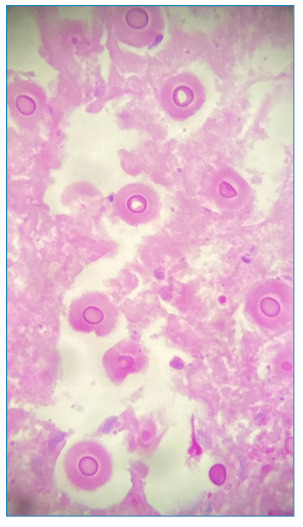

Paracoccidioidomycosis mimicking mycetoma.